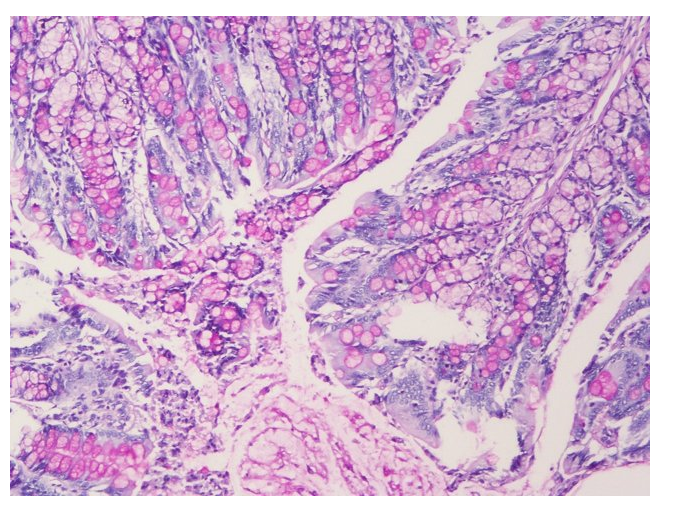

PAS染色又称过碘*酸雪夫染色,糖原染色;一般用来显示糖原和其他多糖物质。还可以观察肾小球基底膜、结肠杯状细胞中性黏液物质、阿米巴滋养体和垂菌的着色。

PAS阳性为红色:细胞核蓝色。

文献和实验【原理】 过碘酸-雪夫(Pexiodic acid-schiff,PAS)染色又称糖原染色。胞浆内存在的糖原或多糖类物质(如黏多糖、黏蛋白、糖蛋白、糖酯等)中的乙二醇基(CHOH-CHOH)经过碘酸(Periodic acid)氧化,转变为二醛基(CHO-CHO),与雪夫(Schiff)试剂中的无色品红结合,形成紫红色化合物而沉积于胞浆中糖原类物质所存在的部位。该反应称为过碘酸-雪夫(PAS)阳性反应。医学教育|网搜集整理

组织形态染色 苏丹黑B染色 染色含切片 4%多聚甲醛固定,冰冻切片。对组织内脂质(如脂滴)染色 Masson染色 染色 观察组织纤维化和肌纤维的鉴别及组织纤维化程度 天狼猩红染色 染色 观察组织纤维化程度,及偏振光进行胶原亚型的分区 PAS糖原染色 染色 观察肝脏、肌肉等组织内糖原的变化; 肠胃肺支气管等杯状细胞酸性粘液物质变化 阿利新蓝染色 染色